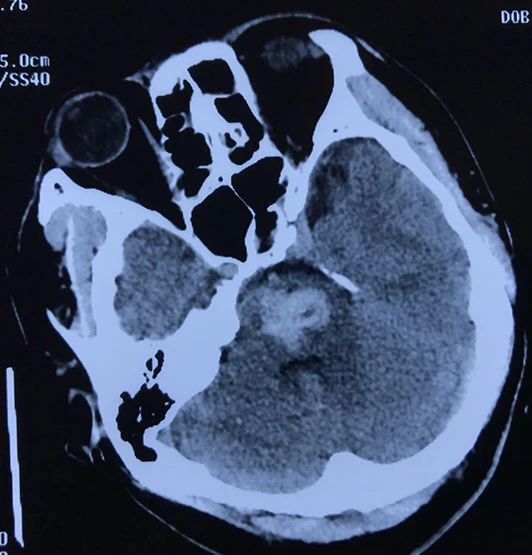

术后磁共振显示脑干病变消失